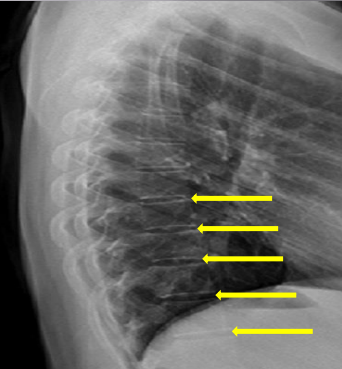

Pedicle shadows

Vertebral waist

Inferior endplate tips

Superior endplate tips

Disc spaces

End plate tips